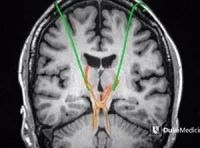

In the journal report, the researchers discuss the common use of CT scans, noting the risks that excessive exposure to radiation may pose for children and adolescents. Also, since CT scans yield no signs of traumatic injury to structures of the brain in most cases of SRC, Dr. Ellis et al. recommend that use of CT should be limited to the emergency room setting in evaluating acutely injured patients in whom clinical signs or symptoms suggest the possibility of skull fracture or intracranial haemorrhage.

While neuroimaging does not reveal pertinent findings in most SRC cases, the researchers stress "the need to consider MRI in paediatric patients with focal neurological deficits, worrisome symptoms, or abnormal or inconclusive CT findings," adding that MRI "should also be considered in paediatric patients with persistent symptoms for which the definition is unclear."